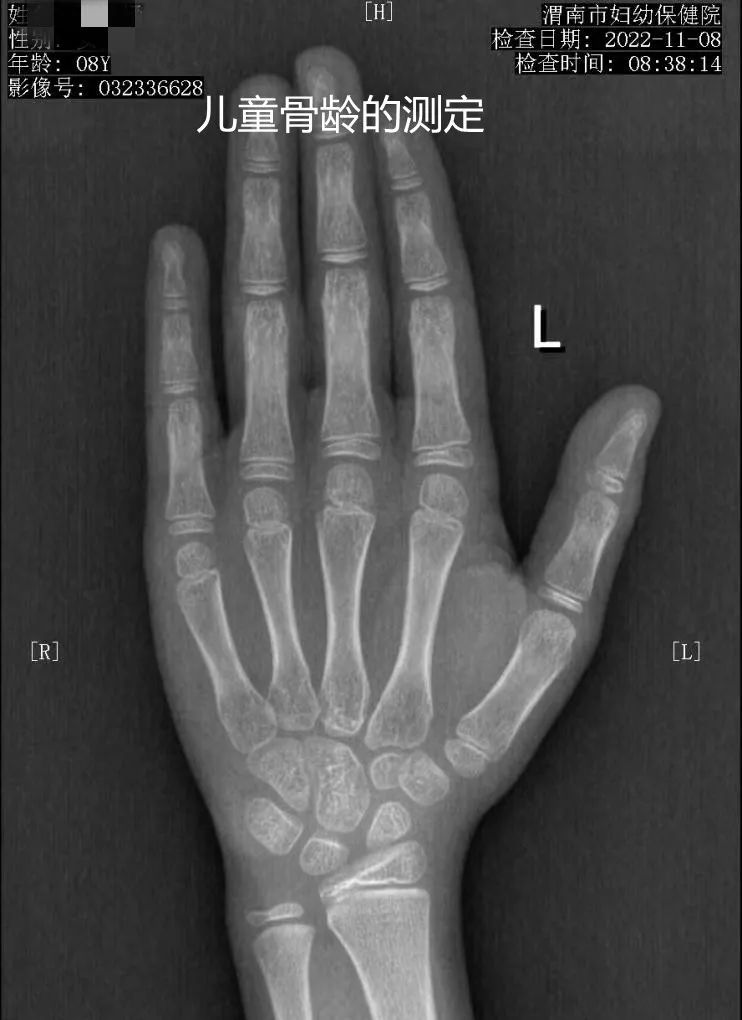

放射"摄影作品"

乳腺疾病的诊断与体检筛查